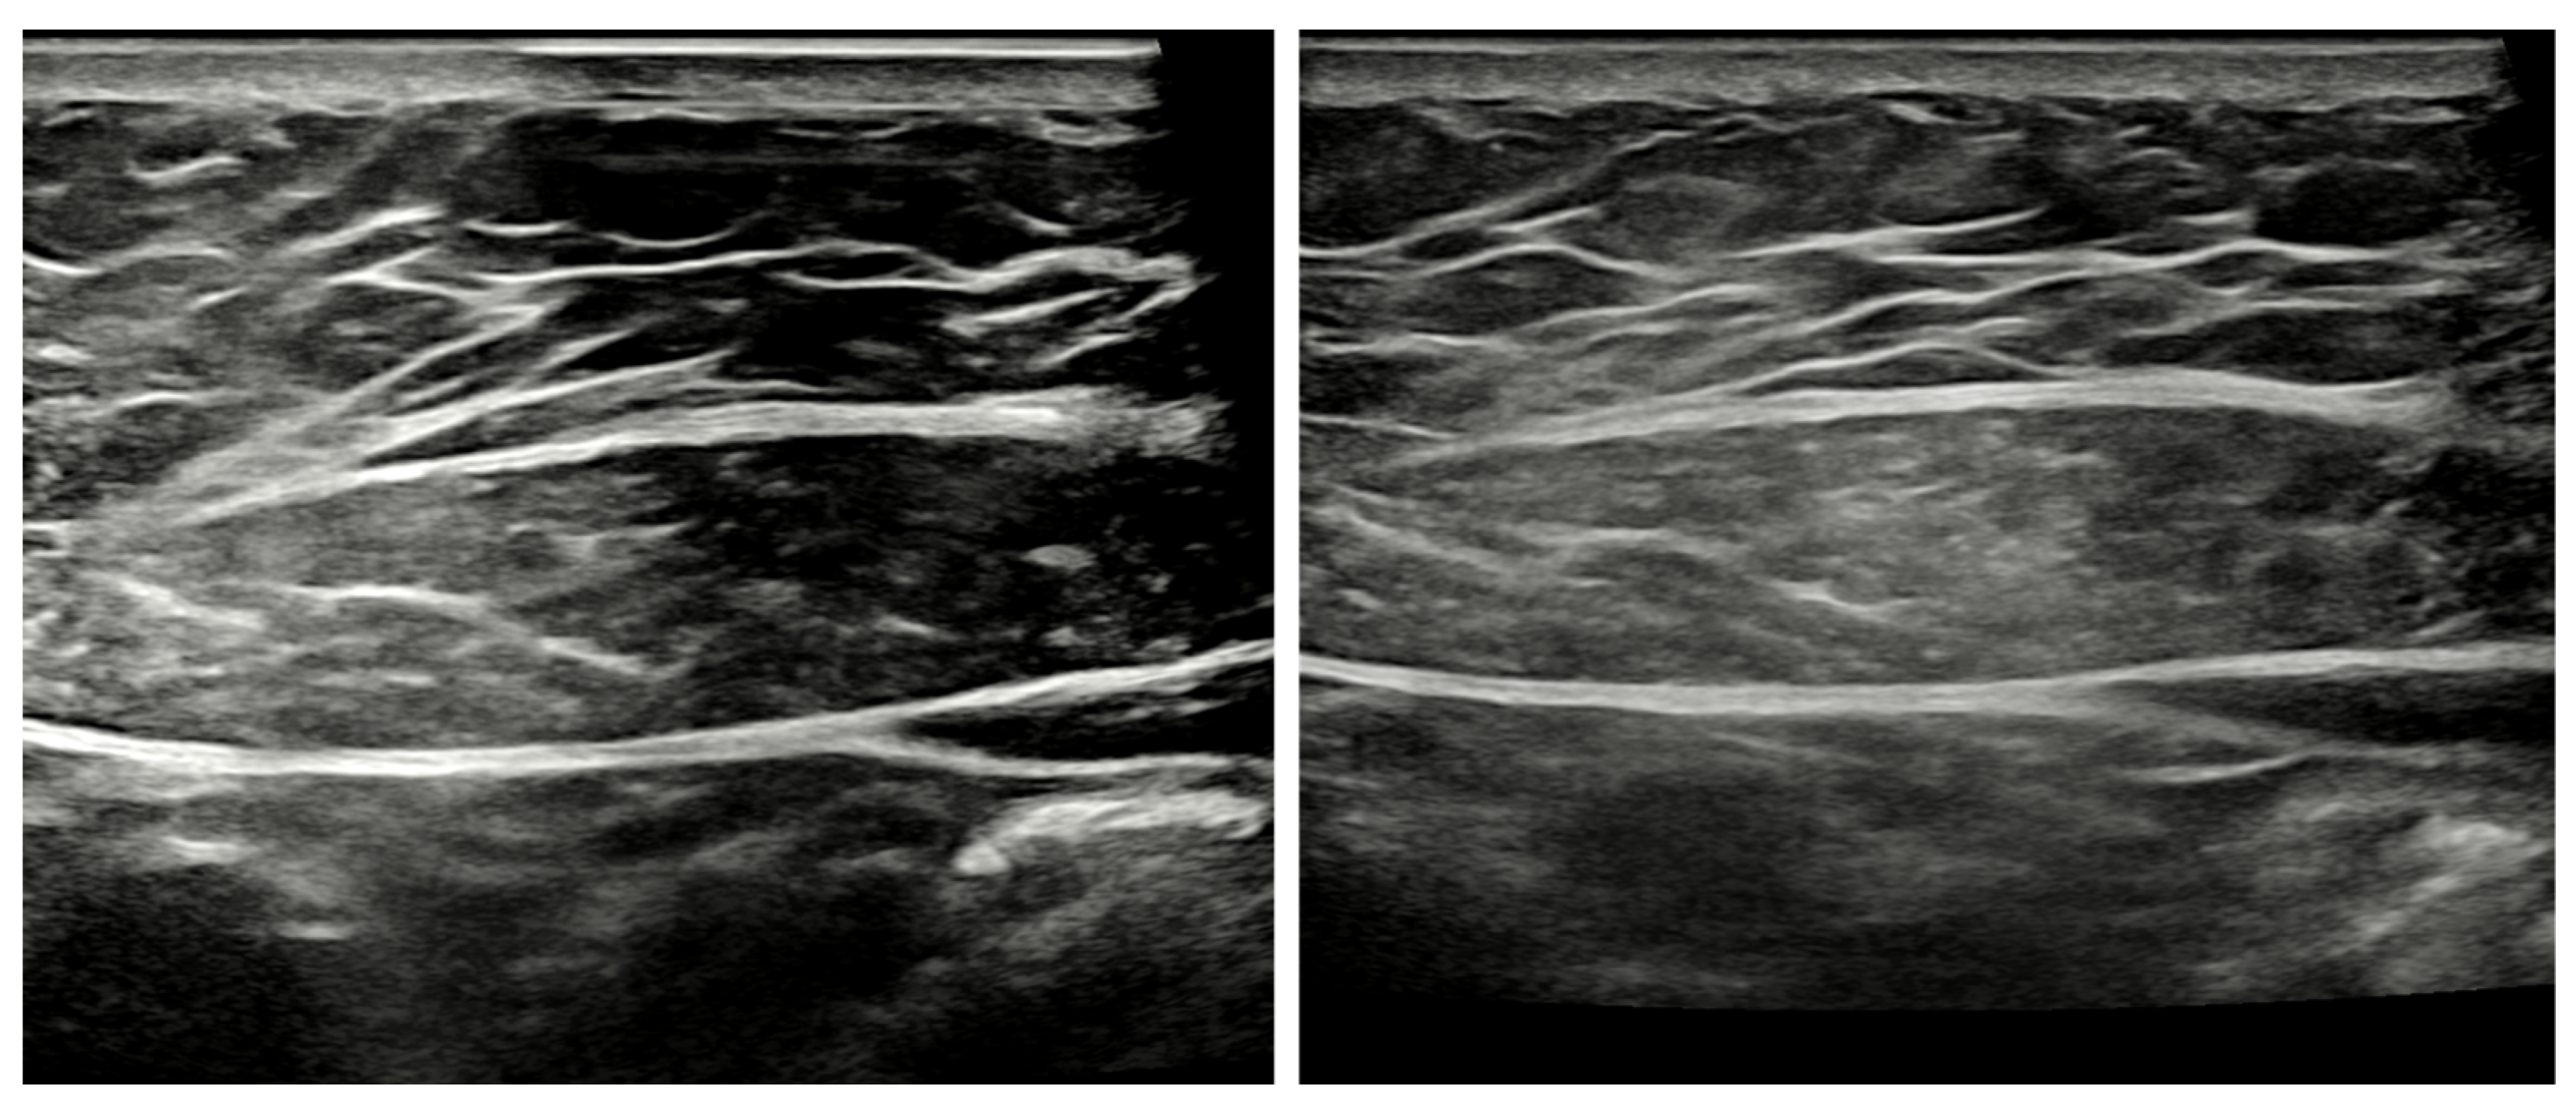

Figure 2.

Ultrasound images of a representative subject with PU (left) and No_PU (right).

The changes in the thicknesses of the fascia and muscle according to absorber usage on B-mode images were compared using image analysis and statistical programs. When comparing the thicknesses of RA, SF, and DF, RA was 12.15 ± 2.73 mm and 11.64 ± 2.75 mm with No_PU and PU, respectively; however, no significant difference (p = 0.260) was observed. Likewise, the thicknesses for SF were 0.93 ± 0.28 mm and 0.89 ± 0.24 mm with No_PU and PU, respectively; however, the difference was insignificant (p = 0.318). For DF, the thicknesses were 0.89 ± 0.31 mm and 0.78 ± 0.21 mm with No_PU and PU, respectively; however, there was no significant difference (p = 0.122) (Table 1 and Figure 2). The inter-rater reliability of the thickness was high (Cronbach’s α = 0.998).